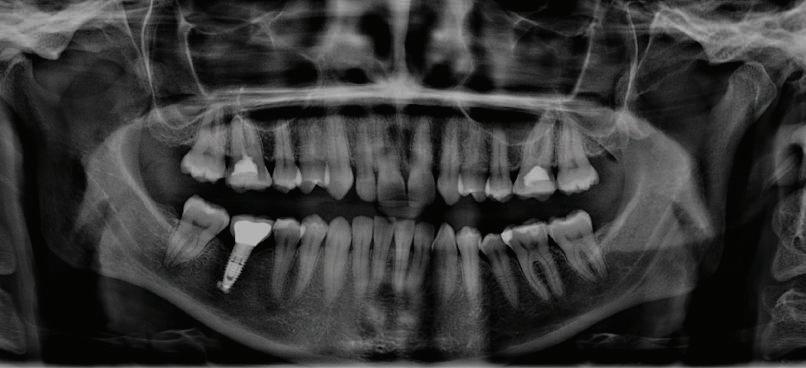

Dental Tribune Bulgarian Edition / октомври 2022 г.16 клиничен случай с алайнери Г орният латерален ре зец е вторият найчесто вродено липсващ зъб.1,2 Поради разполо жението му във видимата зона на усмивката лечение то на подобни случаи нала га мултидисциплинарен под ход, целящ отличен функцио нален и естетичен резултат. Налице са няколко лечебни мо далности, свързани с различ но разпределение на място то: първият вариант е орто донтско отваряне на място и възстановяване на липсва щия зъб с конструкция, под държана от съседните зъби3 или от имплант4, докато при втория подход разстоянията се затварят и премоларът заема мястото на канина.5 Изборът на лечебен подход трябва да бъде направен съв местно от зъболекар и паци ент въз основа на очакванията на последния и предвиди мостта на лечението. Множе ство фактори влияят върху това решение, като напри мер типа малоклузия, размера, формата и цвета на кучеш ките зъби6, оклузалните вза имоотношения (овърджет и овърбайт), лицевия профил, дължината на зъбната дъга и несъответствията в разме ра на зъбите.7 В настоящата публикация се разглежда случаят на жена в зряла възраст с вродена лип са на горен ляв латерален резец. Бяха приложени про зрачни алайнери за отваряне на място за единичен им плант и бяха постигна ти функционална оклузия и отлична естетика. ПРЕДСТАВЯНЕ НА СЛУЧАЯ Диагноза Пациентката бе на 32 годи ни, когато лечението започна, и първоначалното ѝ състоя ние бе следното (фиг. 1–3): липсващ горен ляв латерален резец; клас II, подклас I малоклузия; отклонение на горната сре динна линия вляво; Доклад на клиничен случай ЛЕЧЕНИЕ С АЛАЙНЕРИ НА ПАЦИЕНТ С АГЕНЕЗИЯ НА ЛАТЕРАЛЕН РЕЗЕЦ Д-р Iro Eleftheriadi и д-р Christodoulos Laspos, Гърция и Кипър Фиг. 1a–h Предоперативни лицеви и интраорални снимки. Фиг. 2a–e Дигитални модели преди началото на лечението. Фиг. 3 Панорамна снимка преди лечението. Фиг. 1a Фиг. 1d Фиг. 1f Фиг. 2a Фиг. 2d Фиг. 2b Фиг. 2e Фиг. 3 Фиг. 2c Фиг. 1b Фиг. 1e Фиг. 1g Фиг. 1h Фиг. 1c

Dental Tribune Bulgarian Edition / октомври 2022 г. 17клиничен случай с алайнери леко струпване в долната че люст; несъответствие по Болтън (мандибуларен излишък от 3.06 мм във фронталната зона и общо 1.47 мм); издължено лице с лицева аси метрия; конвексен профил с ретруди рана долна челюст и проми нентен нос. На мястото на зъб #46 бе на лице имплант, а зъби #16 и 26 са ендодонтски лекувани. Тези зъби бяха асимптоматич ни, затова бе взето решение да се прави релечение само при нужда. Мъдреците липсваха. Анализът на телерентгеногра фията (фиг. 4) показа ретрог натна мандибула (SNB: 74.2°) и нормална инклинация на резците както в

Цели на лечението и лечебен план Целите на лечението бяха следните: нивелиране и подреждане на зъбите и в двете зъбни дъги; отваряне на пространство за липсващия латерален резец; коригиране на отношенията при канините и моларите до клас I; и корекция на отклонението на срединната линия. Лечебният план включваше: корекция на отношенията при кучешките зъби и мола рите до клас I с дистализира не на максилата; отваряне на пространство в областта на #22 за поставя не на единичен имплант; корекция на срединната ли ния; и създаване на място за раз ширяване на зъб #12 и апрок симална редукция в долната челюст с цел подобряване на несъответствието по Болтън и осигуряване на подобра оклузия. Изпълнение на лечебния план Този случай бе изпълнен със системата за алайнери Invisalign (Align Technology). Одобреният първоначален лечебен план предвиждаше 49 алайне ра с дистализиране на задни те горни зъби до клас I (прибли зително с около 3.5 мм; фиг. 5). За бъдещия имплант в областта на липсващия латерал бе планирано пространство от 6.5 мм, докато във фронталния сегмент на долната челюст бе предвидена апроксимална редук ция. В дясната страна бутон за ластици клас II бе поставен на зъб #47 вместо на зъб #46, за да не се увреди короната на импланта. Понеже пациентката жи вееше в чужбина,

следните казуси: недобра оклу зия в дисталните зони по вре ме на дистализирането на гор ната челюст и накланяне на зъб #21 (фиг. 7). Последното се дължи на липсата на компози тен атачмънт на този зъб, каквото не бе зададено в пър Фиг. 4 Телерентгенография и цефалометричен анализ преди началото на лечението. Фиг. 5a–e Одобреният първоначален лечебен план. Фиг. 6a–h Снимки по време на лечението, показващи нуждата от внасяне на някои корекции. Фиг. 4 Фиг. 5a Фиг. 5d Фиг. 6a Фиг. 6d Фиг. 6f Фиг. 6b Фиг. 6e Фиг. 6g Фиг. 6h Фиг. 6c Фиг. 5e Фиг. 5b Фиг. 5c

Dental Tribune Bulgarian Edition / октомври 2022 г.18 воначалния план. Тези пробле ми бяха адресирани чрез допъл нителна поръчка на алайнери с торк контрол и зададено екст рудиране на задните зъби с цел установяване на добри оклузал ни контакти в дисталните об ласти, като бяха предвидени и оптимизирани атачмънти с контрол над корените за корекция на ангулацията на макси ларните резци (фиг. 8). Резултати от лечението Панорамната рентгено графия след ортодонтското лечение показа благоприятна паралелна позиция на съседни те зъби, подходяща за поставя не на имплант в областта на #22, както и конвергенция на ко рените на зъби #44 и 45 (фиг. 9), но преценихме, че няма да от деляме допълнително лечебно време за коригирането ѝ поради факта, че пациентката бе мно го доволна от постигнатия до момента резултат. След при ключване на лечението бяха постигнати отлични взаимо отношения клас I при мола рите и канините, а срединни

ти и клас II ластици е устано вено, че осигурява достатъч на дистализация без промяна на лицевата височина.23 Както се видя от цефалометричния анализ, точно това бе постиг нато и в представения случай като се има предвид, че лице вата височина остана същата като първоначалната. Предвид леката тенденция към дистал Фиг. 8a–e Поръчаните допълнителни алайнери. Фиг. 9 Панорамна рентгенография след края на лечението. Фиг. 10a–c Странични (а и с) и фронтална интраорални снимки след края на ортодонтското лечение и поставянето на импланта (b). Зъб #12 все още не беше протезиран. Фиг. 11а и b Оклузални снимки след ортодонтското лечение. Фиг. 7a Фиг. 8a Фиг. 7d Фиг. 8d Фиг. 9 Фиг. 10a Фиг. 10b Фиг. 10c Фиг. 11bФиг. 11a Фиг. 7b Фиг. 8b Фиг. 7e Фиг. 8e Фиг. 7c Фиг. 8c Фиг. 7a–e Интраоралната ситуация по време на лечението. клиничен случай с алайнери